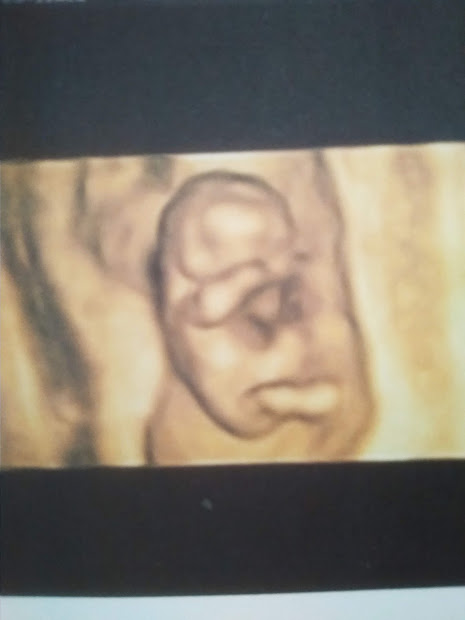

Through a friend in Queretaro, I was able to find an English-speaking obstetrician here as well, which was wonderful, because I was not feeling ready to navigate all of that yet. She had already done all the research for me, since she too is pregnant (and speaks Spanish fluently!). I got an appointment a little over a week after we returned to Mexico, and she did an ultrasound right there in her office, with the amazing image displayed below. It was an incredibly clear ultrasound, and I was able to see the baby rubbing its eyes! And… the OB told me that there is no other mass – just a healthy baby!